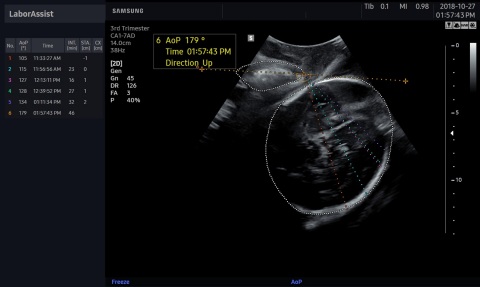

SANTA CLARA, Calif.--(BUSINESS WIRE)-- What’s New: Samsung Medison and Intel are collaborating on new smart workflow solutions to improve obstetric measurements that contribute to maternal and fetal safety and can help save lives. Using an Intel® Core™ i3 processor, the Intel® Distribution of OpenVINO™ toolkit and OpenCV library, Samsung Medison’s BiometryAssist™ automates and simplifies fetal measurements, while LaborAssist™ automatically estimates the fetal angle of progression (AoP) during labor for a complete understanding of a patient’s birthing progress, without the need for invasive digital vaginal exams.

During labor, LaborAssist helps physicians estimate fetal AOP and head direction. This enables both the physician and patient to understand the fetal descent and labor process and determine the best method for delivery. There is always risk with delivery and a slowing progress could result in issues for the baby. Obtaining more accurate and real-time progression of labor can help physicians determine the best mode of delivery and potentially help reduce the number of unnecessary cesarean sections.

“LaborAssist provides automatic measurement of the angle of progression as well as information pertaining to fetal head direction and estimated head station. So it is useful for explaining to the patient and her family how the labor is progressing, using ultrasound images which show the change of head station during labor. It is expected to be of great assistance in the assessment of labor progression and decision-making for delivery,” said Professor Min Jeong Oh, MD, PhD, Department of Obstetrics and Gynecology, Korea University Guro Hospital in Seoul, Korea.